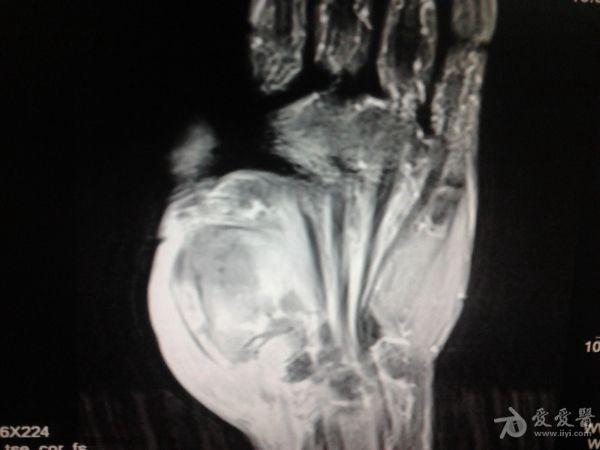

右第一掌骨、大多角骨肿瘤

男性患者,81岁,右手肿痛3个多月。无任何其它症状。体查:右手第一掌骨部肿胀明显,第一指活动受限,余四指活动可,腕关节活动小部分受限,活动时会痛。影像学检查如下。活检示:弥漫性大B细胞淋巴瘤。大家看看需不需要截肢?现在有人主张手术;有人主张不手术,直接化疗。大家有什么看法?

从以上资料看已经影响到腕关节了,还是截吧,不能姑息